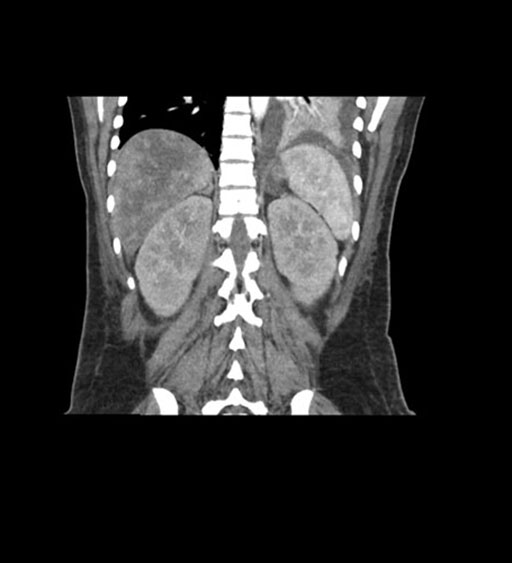

Coronal Venous